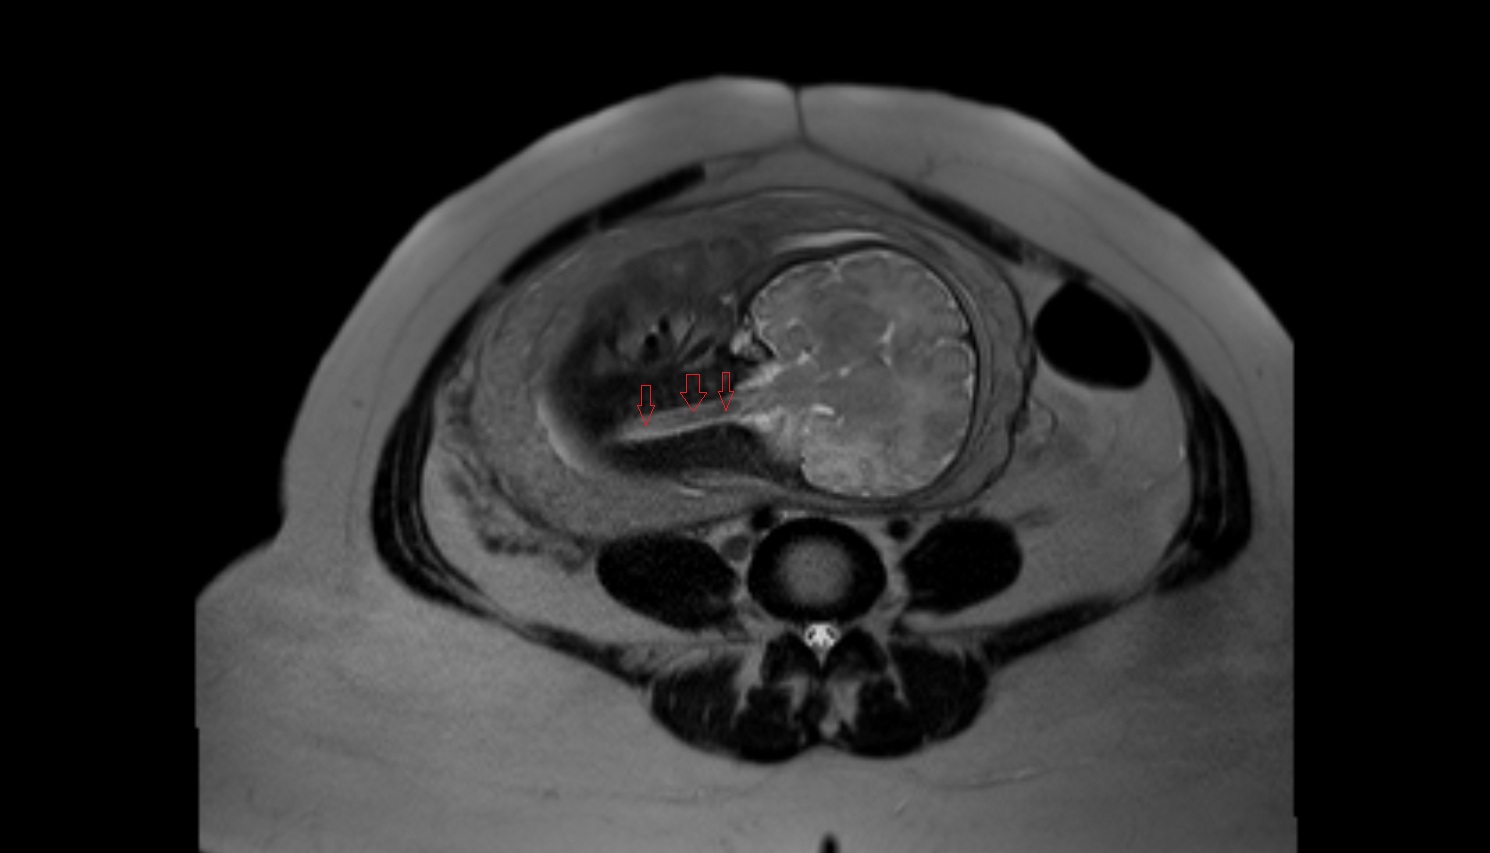

- Fetal brain

- Fetal caudate nucleus

- Fetal thalamus

- Fetal cerebellum

- Fetal occipital lobe

- Fetal temporal lobe

- Fetal parietal lobe

- Fetal frontal lobe

- Fetal lateral ventricle